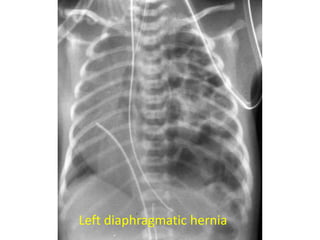

Left diaphragmatic hernia

• Diaphragmatic hernia